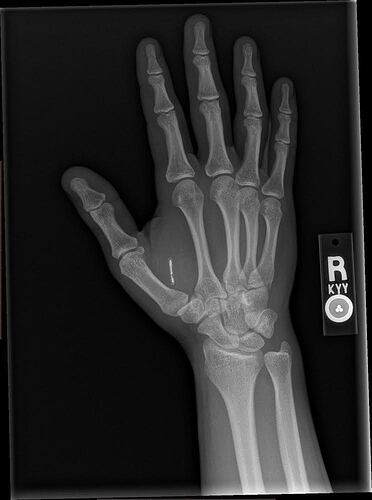

Little Titan update: approaching 2 years with it in and no complaints so far. Nothing strange has happened with it. I’ve bumped it causing significant pain two or three times over the years but I’d compare them to a bad toe stubbing. Painful for a minute, then sore fore less than a day. I can say the sensitivity has slightly decreased since the first 6 months but I suspect my healing tissue was just more sensitive than current tissue. I can still feel the magnets in the airood case in my left pocket as my hand swings by my leg while I walk (that’s one of my favorite things). Here are some x-rays I got this year of both my titan and my NExT installs. NExT chip was installed by a nurse I know Thanksgiving of 2022. No numbing, but the back of the hand wasn’t a very painful place and it went smooth and well.